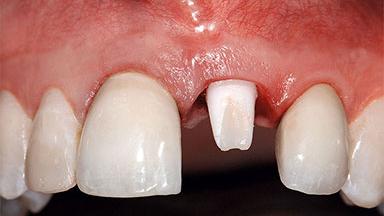

A healthy 37-year-old female patient was referred for a consultation on the replacement of missing tooth 21 with an implant-supported restoration. She stated that several years previously the tooth had been traumatically avulsed following a motor vehicle accident. The tooth was replaced with a three-unit fixed partial denture (FPD) immediately afterwards. Over time, she became disillusioned with the FPD and looked for a different option, including orthodontic therapy. She presented still in her orthodontic appliances, with the pontic sectioned free from the FPD but attached to the archwire. Her orthodontist felt that orthodontic treatment had been successfully completed, but nevertheless referred her before removing the appliances in case adjustments were necessary.

Width of Edentulous Span 1 tooth (>= 7 mm) 1 tooth (< 7 mm) 2 teeth or more

Soft Tissue Anatomy Intact Defective